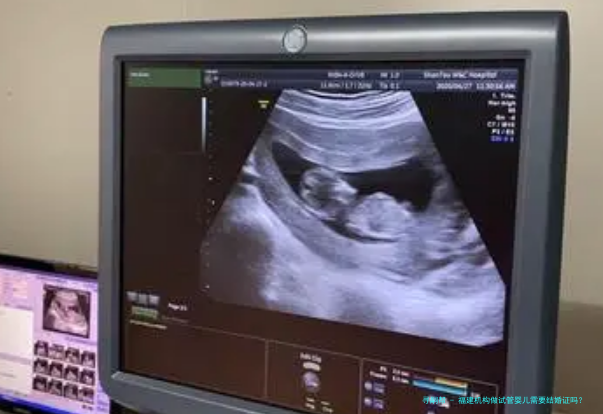

在福建省,如若夫妻双方盼望通过机构进行试管婴儿技术(即是辅助生育技术)来实现生育心愿,通常情况下需要提供成婚证。这是因为根据国内的相关法律条规和伦理要求,辅助生殖服务主要面向合法婚姻内的夫妇开放,以保证医疗服务符合社会伦理尺度,并保障儿童的正当权益。